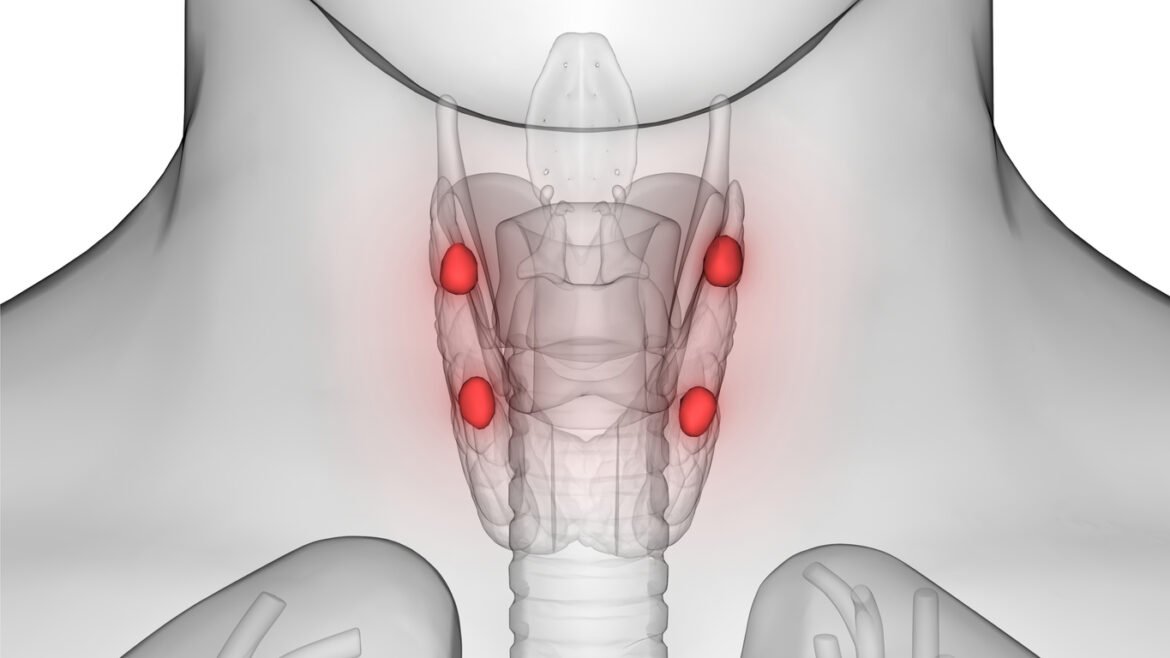

Hypoparatyreoidism är en sällsynt hormonbristsjukdom som oftast uppstår på grund av att bisköldkörtlarna skadas av misstag i samband med sköldkörtelkirurgi.

3D Illustration of Human Body Glands Anatomy (Parathyroid glands)

- Hypoparatyreoidism beror på brist på parathormon (PTH).

- PTH-bristen leder till:

- Kalciumbrist

- Höga fosfatnivåer

- Ökad kalciumutsöndring i urinen

- Brist på magnesium och D-vitamin